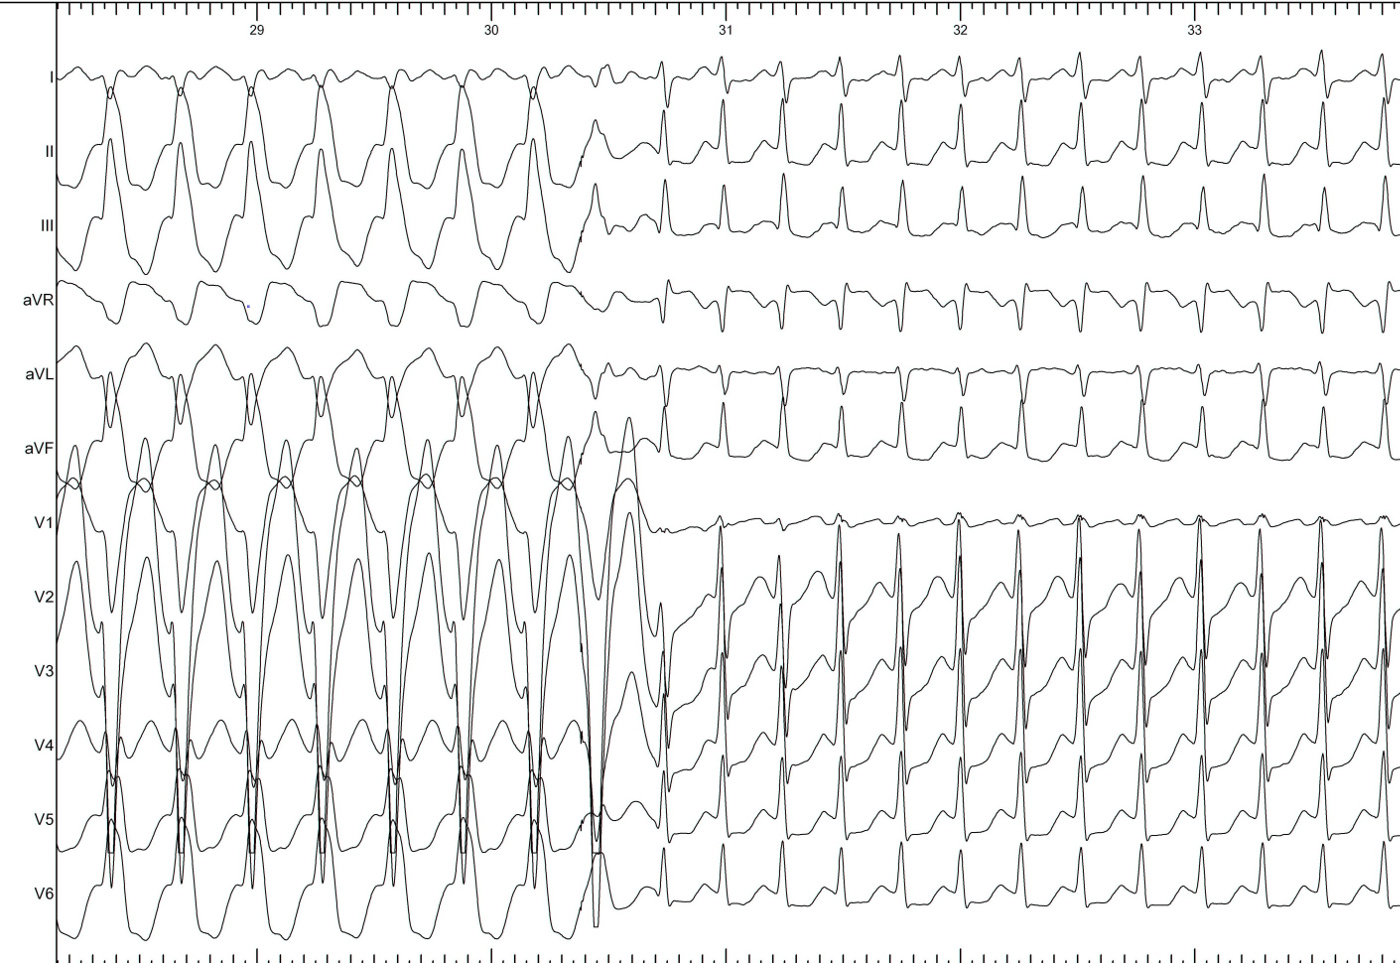

Narrow QRS tachycardia, central atrial activation, very short VA

typical_avnrt.jpg

Commonest Setting

• Regular narrow QRS tachycardia

• 1:1 VA

• Atrial activation central

• VA > 70 ms

SVT

svt.jpg